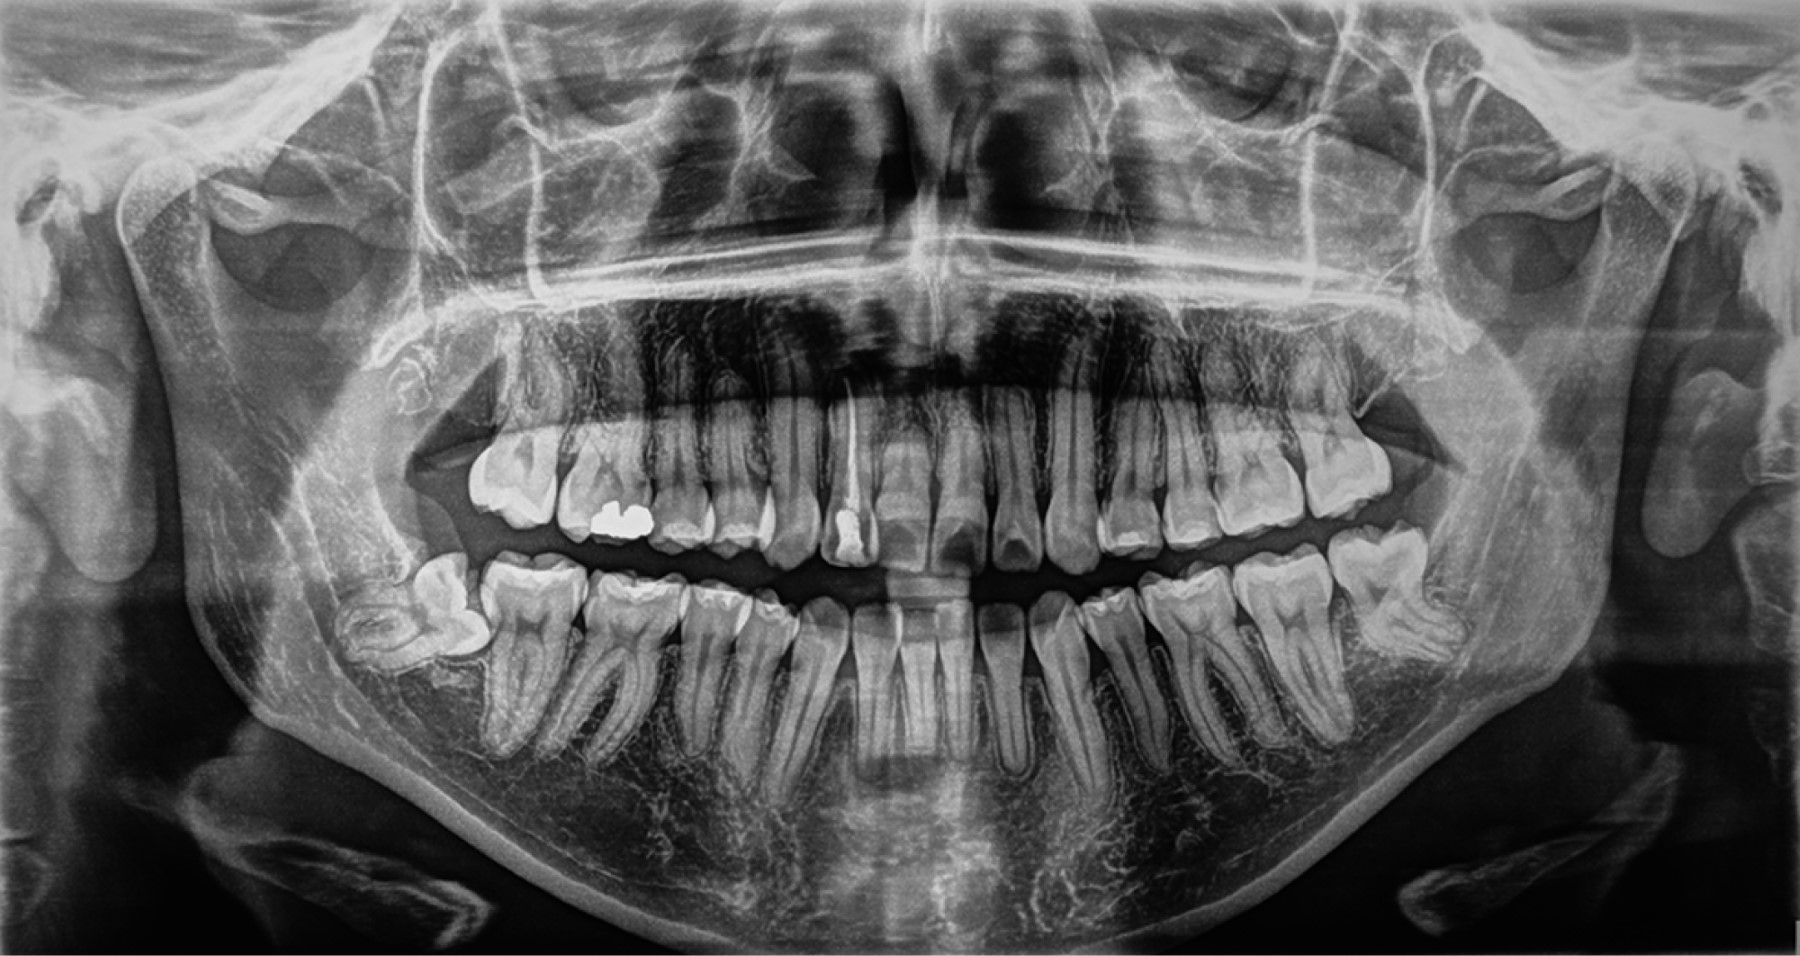

La duración del tratamiento fue de 32 meses, se alcanzó la coordinación de ambas arcadas, se corrigió el exceso de crecimiento vertical de la paciente, se consiguió clase I canina bilateral, sonrisa con arco positivo, correcta guía anterior (overjet y overbite), coincidencia de las líneas medias, se eliminó la mordida borde a borde en sector anterior y la mordida cruzada en sector posterior derecho (Figuras 5 y 6). En el examen radiográfico se observó paralelismo radicular y las adecuadas inclinaciones de los incisivos (Figuras 7 y 8, Tabla 2).